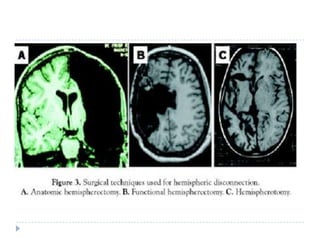

Cerebral hemispherectomy or hemispherotomyIt should be considered in patients where seizure focus is limited to one hemisphere and patient already has disabling hemiparesis with useless hand. It has been reported to decrease seizure frequency and improve developmental quotient in children with catastrophic hemispheric epilepsy of diverse aetiologies such as malformations of cortical development, Rasmussen’s encephalitis, Sturge-Weber syndrome, and remote vascular insults.

Cerebral hemispherectomy orhemispherotomyIt should be considered in patients where seizure focus is limited to one hemisphere and patient already has disabling hemiparesis with useless hand. It has been reported to decrease seizure frequency and improve developmental quotient in children with catastrophic hemispheric epilepsy of diverse aetiologies such as malformations of cortical development, Rasmussen’s encephalitis, Sturge-Weber syndrome, and remote vascular insults.